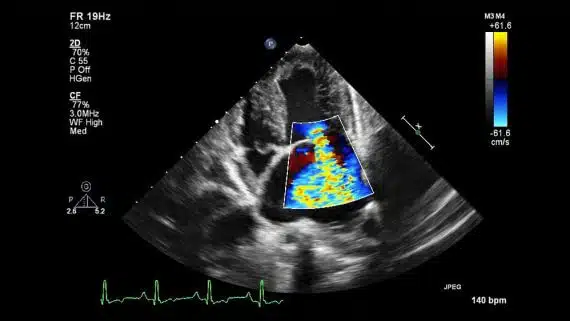

Doppler echocardiography

This method is used to evaluate and measure the blood flow through the valves and chambers of the heart. The amount of blood that pumps out with each beat is the indicator of the heart’s functioning. Doppler echocardiography can also detect blood flood abnormalities within the heart septum.